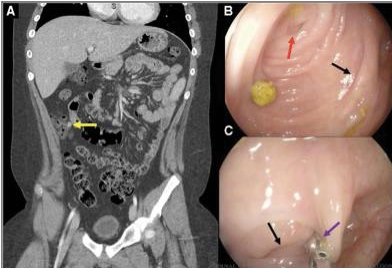

12 yo boy with progressively worsening RLQ pain. CT showing an 11mm structure near the cecum. Colonoscopy shows a cecal diverticula. What is the next best step? Answer and learn more 👉 bit.ly/3htf9YP?utm_so… #imageofthemonth #quickpoll

JPGNonline's tweet image. 12 yo boy with progressively worsening RLQ pain.  CT showing an 11mm structure near the cecum. Colonoscopy shows a cecal diverticula.

What is the next best step?

Answer and learn more 👉 bit.ly/3htf9YP?utm_so…

#imageofthemonth #quickpoll